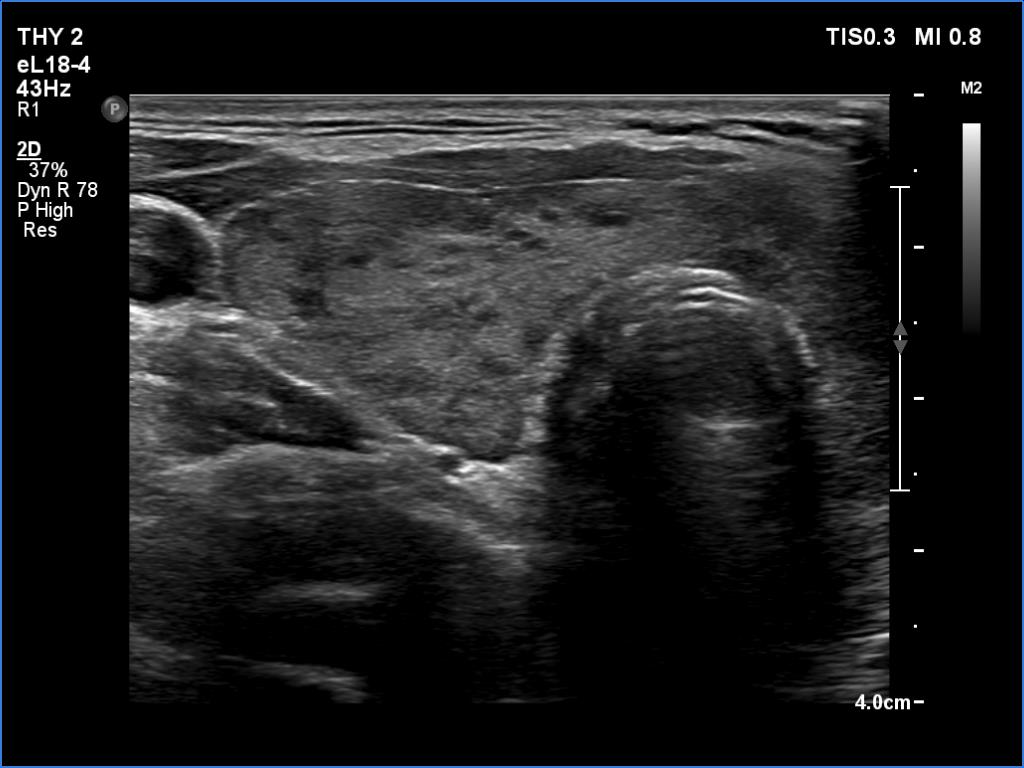

Right lobe, transverse scan

Clinical data: A 35-year-old woman was referred for a newly diagnosed hyperthyroidism. The patient had typical complaints, including elevated heart rate and weight loss.

Comment.

This is the typical course of a non-relapsing Graves' hyperthyroidism. As the hormone results improve, both the size of the initially enlarged goiter and the degree of hypoechogenicity decrease.